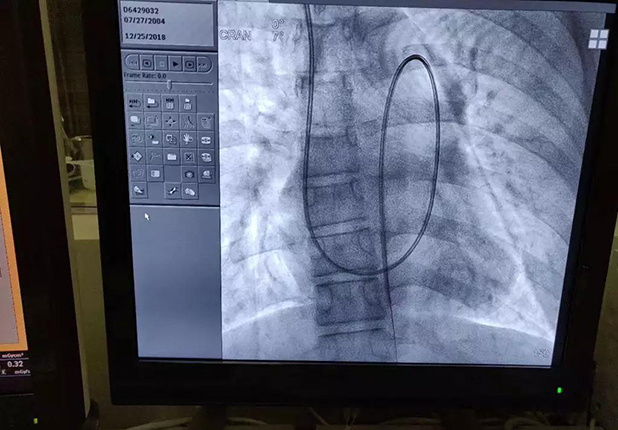

一例14岁动脉导管未闭合并肺动脉高压患者经颈静脉至降主动脉的漂浮导管路径